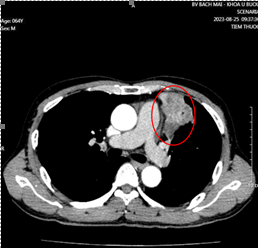

Hình 3: Nhu mô hạ phân thùy VII có vài khối, nốt kích thước lớn nhất 33x26mm giảm tỷ trọng trước tiêm, ngấm thuốc thì động mạch (vòng tròn đỏ), thải thuốc thì tĩnh mạch cửa (vòng tròn).

Cắt lớp vi tính ổ bụng có tiêm thuốc cản quang: